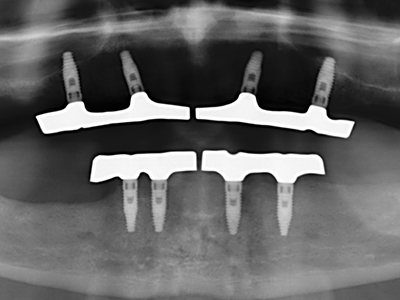

Fig. 15: The one-year follow-up x-ray examination shows stable conditions at the bone level.

Fig. 16: The intraoral conditions are also stable with embedding of the implants in keratinized gingiva.